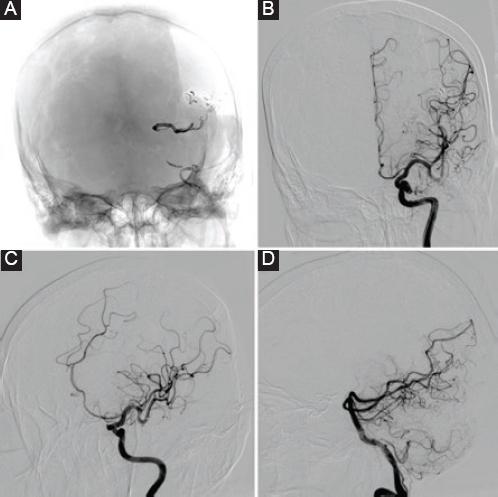

Mujer de 51 años, sin antecedentes médicos ni quirúrgicos, con historia de cefalea de 30 años de evolución que se presentaba de tres a cinco veces por mes, de tipo holocraneana, pulsátil, de moderada intensidad, que cedía con la ingesta de antiinflamatorios no esteroideos, sin alteraciones neurológicas asociadas. Incidentalmente, por el estudio de una masa en el cuello que se protocolizó con estudios de imagen, se evidenció un cortocircuito arteriovenoso parietoccipital medial izquierdo, por lo que es referida al servicio de neurocirugía, donde se le realiza angiografía diagnóstica y se encuentra una malformación arteriovenosa de 33 × 26 × 32 mm en la región parietooccipital izquierda, que recibía suministro sanguíneo a través de las arterias cerebral media izquierda y cerebral posterior homolateral, con drenaje venoso superficial hacia el seno sagital superior y el seno transverso, clasificándose como de grado III en la escala de Spetzler-Martin, con aneurismas proximales de 3.1 × 2 × 3.3 mm en el segmento M1 y de 5.7 × 6.2 × 7 mm en la bifurcación de la arteria cerebral media izquierda. Se plantea como manejo inicial la embolización de los aneurismas proximales con material cohesivo, pero durante la intervención endovascular se observa una compresión de la arteria temporal posterior, por lo cual se decide retirar el material cohesivo y dar por concluido el procedimiento de manera incompleta. Posteriormente se plantea embolizar la malformación arteriovenosa a través de la arteria occipital izquierda, logrando una embolización del 90% (Fig. 1), y en un segundo tiempo quirúrgico se realiza el clipaje del aneurisma de mayor tamaño, a través de un abordaje pterional izquierdo, monitorizando con Doppler transcraneal las velocidades de flujo sanguíneo durante todo el procedimiento (Fig. 2). Finalmente se concluye sin complicaciones y la evolución en su recuperación es adecuada. A los 6 meses se realiza una craneotomía para la resección completa de las malformaciones arteriovenosas cerebrales, que concluye sin complicaciones, con sangrado mínimo y adecuada recuperación neurológica (Fig. 3).

Figura 3 A: control angiográfico a los 6 meses del clipaje de los aneurismas de arteria cerebral media izquierda y tras la resección quirúrgica de la malformación arteriovenosa parietooccipital izquierda Spetzler-Martin II. B: angiografía con sustracción digital y proyección anteroposterior. C: angiografía con sustracción digital y proyección oblicua. D: angiografía con sustracción digital y proyección lateral.